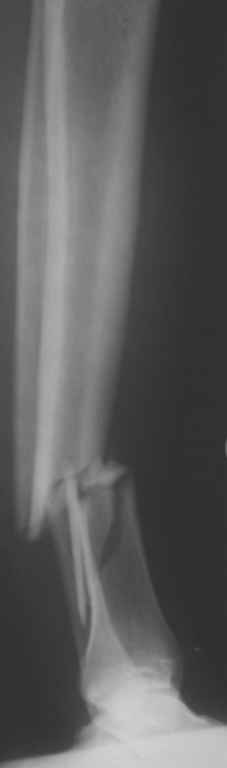

Консультировал рентгенограммы после интрамедуллярного остеосинтеза

бедра гвоздем Fixion. Пациенту объяснили, что важнее сохранить

перелом "закрытым", чем  фиксировать осколок из дополнительного

разреза. Сами собираемся оперировать голень и думаем, что без

"открытия" места перелома не обойтись.